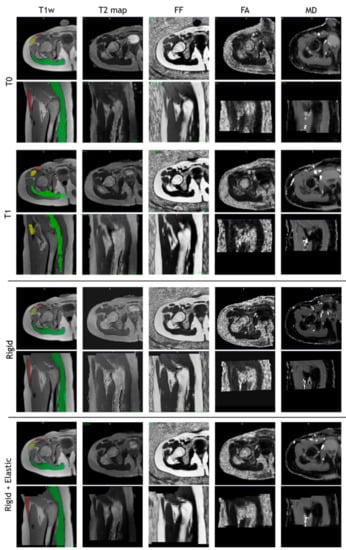

The images of a sample subject after all registration steps are shown in Figure 10. Multimodal acquisitions are shown registered on their intra-session T1-w scan.

Figure 10. T1-w, T2 map, fat fraction, fractional anisotropy, and mean diffusivity map after intra-session rigid registration and rigid and non-rigid registration steps of a sample subject.